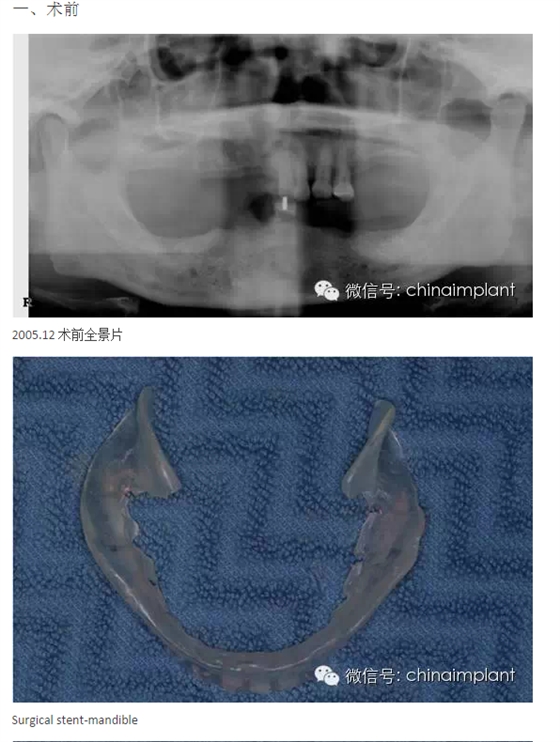

本案例已經(jīng)將近10年了(2005年12月),但是修復(fù)效果個(gè)人認(rèn)為很不錯(cuò),所以拿出來和大家分享。

從修復(fù)全景片上看到牙齒排列非常好